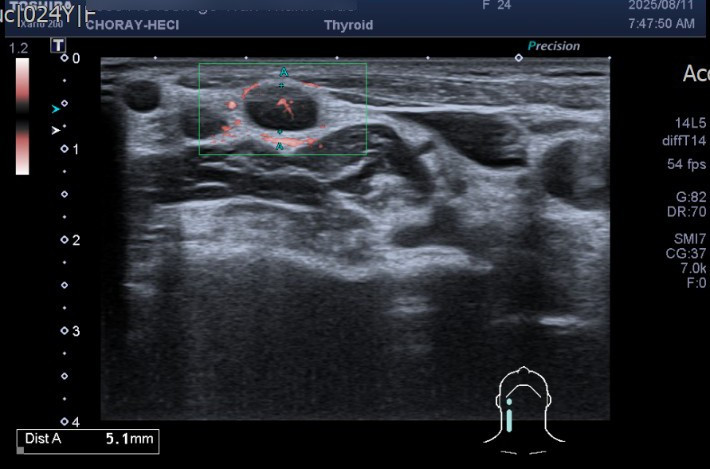

tuyen-giap-k.jpg

Kết quả chọc hút tế bào tuyến giáp, ghi nhận có tế bào ác tính (carcinoma giáp nhú)